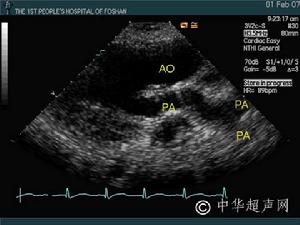

4.超声心动图左房粘液瘤在左心腔内见到异常的点片状反射光团,活动于左房、左室之间,收缩期回到左房腔,舒张期达二尖瓣口进入左室,二尖瓣前叶EF斜率减低,左房增大。右房粘液瘤异常反射光团在右心腔内,收缩期在右房,舒张期随三尖瓣向右室方向移动或通过三尖瓣口进入右室腔。右房、右室增大。 医学百科网 | YxBaike.Com

3.超声心动图检查显示瘤体随心脏收缩和舒张活动。心血管造影显示心腔内占位性病变,但有一定的假阳性、自有超声心动图,心血管造影较少应用。 医学百科网 | YxBaike.Com